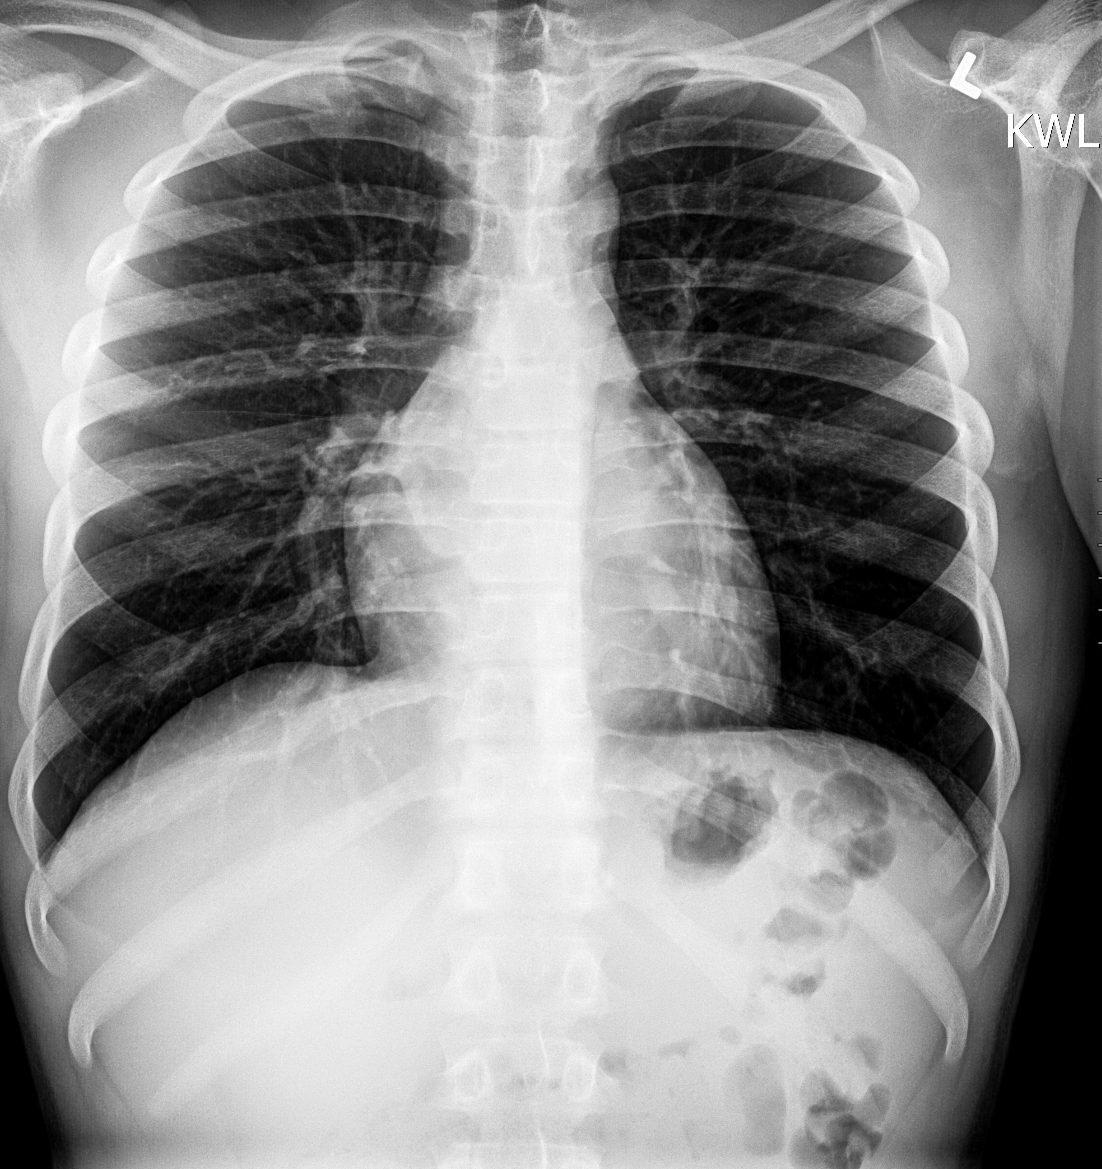

Info Images Findings Impression Reco/Acuity Case Images View Images / Launch Visage Case Notes History 2-month-old presents with decreased right arm movement, increased fussiness, and increased sleepiness for 2 days. Suspected non-accidental trauma. Exam Skeletal survey Prior Study none Dicom View Reference Material

Section 1 Submit Findings CB1550 Findings Skeletal Survey - Technique Check Skull AP/Lat Yes No Cervical and Thoracolumbar spine Yes No Chest X-Ray Yes No Ribs – Left/Right Oblique Yes No Abdominal X-Ray Yes No Pelvis with both hips Yes No Bilateral Humerus, Forearm, Hand Yes No Bilateral Femur, Tibia/fibula, feet Yes No Any additional lateral views of the extremities Yes No The exam is over or under penetrated. Yes No The exam may or may not be limited by overlying structures or soft tissues, body habitus, patient positioning, support devices, or motion. Yes No The area of concern is indicated by the patient, technologist, or care provider. Yes No The area of concern is included on the exam. Yes No Soft Tissues There is soft tissue swelling, indistinctness of fat/muscle planes, gas, or laceration in the area of clinical concern. Yes No There is an effusion, fat pad displacement, or fat fluid level. Yes No There is a radiodense or lucent foreign body. Yes No There are other densities, calcifications, post-surgical changes, or support devices in the soft tissues. Yes No Any support lines/tubes. Yes No Bone There is a break or interruption of the continuity of the cortical or cancellous bone. Yes No There is overriding of the trabeculae with apparent sclerosis. Yes No There is displacement of a fracture fragment. Yes No There is bowing of the bone in addition to the fracture at the apex of the bowed bone concerning for the greenstick. Yes No There is a spiral fracture of the leg concerning for toddler’s fracture. Yes No There is abnormal angulation or bulging of the cortical surface relative to the normal cortex which could be from a buckle or torus fracture. Yes No There is a displaced fragment which may be from avulsion by a tendon, ligament, or joint capsule or from a comminuted or other fracture. Yes No The stress trabeculae or other trabeculae of the cancellous bone are interrupted or otherwise abnormal. Yes No There is subperiosteal or endosteal reaction which could indicate a healing or subacute fracture or other abnormality. Yes No There is hard/soft callus formation. Yes No There is remodeling of the bone. Yes No There is a corner fracture or metaphyseal lesion that could be from nonaccidental trauma. Yes No There are multiple fractures of different ages. Yes No There are vertebral body/spinous process fractures. Yes No There are rib fractures. Location - posterior or lateral. Yes No There is scapular/sternal fracture. Yes No There are fractures of the digits. Yes No There are wormian bones. Yes No There are intrasutural bones. Yes No There is metaphyseal abnormality (lucencies, increased density, erosion) which may be from something other than injury such as stress, metabolic disease (e.g. rickets with loss or distortion of the zone of the provisional calcification), neoplasm (e.g. leukemia), heavy metals, inflammation, or infection. Yes No There are metaphyseal spurs. Yes No There are bony deformities involving multiple bones. Yes No The bones are gracile. Yes No There are non-healing fractures. Yes No There is/are focal or multifocal lytic/lucent, blastic/sclerotic or mixed density lesion(s) or other abnormality. Yes No Overall bone density is increased or decreased with or without thinning or thickening of the cortical or cancellous bone. Yes No Growth plates, ossification centers, apophyses The growth plate(s) is/are abnormal. Yes No There is widening of the physis from a fracture with or without displacement of the epiphysis (Salter-Harris I). Yes No There is a fracture through the physis which then extends into the metaphysis with or without angulation or displacement (S-H II). Yes No There is a fracture through the physis which then extends into the epiphysis and is intra-articular, with or without angulation or displacement (S-H III). Yes No There is a fracture through the metaphysis, physis, and epiphysis which extends into the joint space with or without angulation or displacement (S-H IV). Yes No There is narrowing of the physis from a compression fracture (S-H V). Yes No The apophysis, epicondyle, secondary ossification center, or accessory ossicle is displaced or otherwise abnormal. Yes No The ossification centers are underdeveloped. Yes No Joints and alignment There is an effusion, fat pad displacement, or fat fluid level. Yes No The epiphysis or subchondral bone is fractured, interrupted, flattened, compressed, impacted, displaced, or otherwise abnormal. Yes No There is an intra-articular loose body or chondrocalcinosis. Yes No The joint is widened, narrowed, dislocated, malaligned, or incongruent. Yes No There is pseudoarthrosis. Yes No Other findings There are developmental changes or other anatomic variants or other existing conditions that may or may not be contributing to symptoms which can or should be further evaluated non-emergently or are otherwise incidental. Yes No The remainder of the exam is abnormal for age. Yes No The lungs show focal airspace opacity. Yes No There is pneumothorax. Yes No There is organomegaly. Yes No There is intra-abdominal calcification. Yes No There is displacement of the bowel loops. Yes No There is free intraperitoneal air. Yes No The bowel loops are dilated/obstructed. Yes No There is paraspinal soft tissue abnormality. Yes No